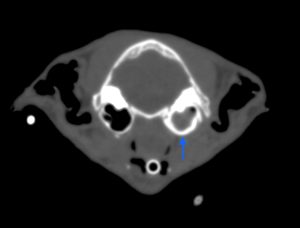

こんにちは。獣医師の永井です。 今回は肺葉捻転についてです。 犬猫の肺はバナナの房のように前葉、中葉、後葉(副…]]>

こんにちは。獣医師の永井です。 今回は肺葉捻転についてです。 犬猫の肺はバナナの房のように前葉、中葉、後葉(副…]]>